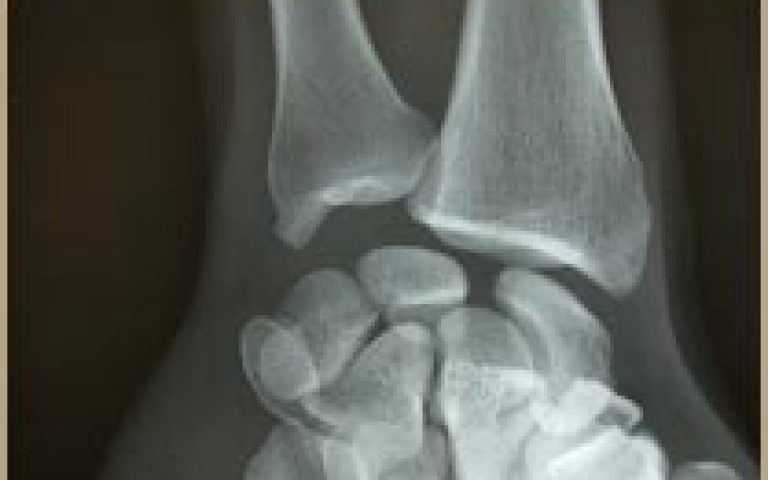

Hand and wrist emergencies Scaphoid fracture

Scaphoid fracture

Hand and wrist emergencies Wrist fracture

Wrist fracture